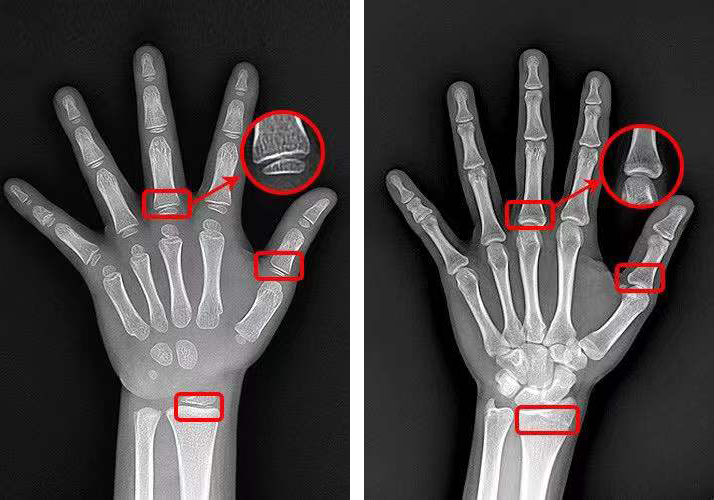

我们看下还有生长空间的孩子生长板是什么样的:

▲左图为4.7岁孩子的生长板,清晰可见

右图为17岁男孩,骨干骺端完全闭合,生长板消失